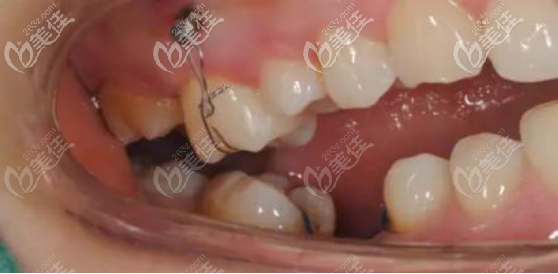

先通過術(shù)前術(shù)后對比圖來看看我露齦笑做正畸的效果吧!改善程度確實很明顯

我的露齦笑經(jīng)過檢查后是骨性的,有些人是牙齦本身就長,還有的人是上唇過短造成的,但是我是骨性問題,上頜骨在垂直方向過度發(fā)育了,所以牙齒有一點點前凸,導(dǎo)致我笑起來的時候露出的牙齦大概有3mm,牙齦露出部分占整個牙的30%左右。

目前我做完露齦笑正畸手術(shù)已經(jīng)有3年的時間了,大家從對比圖片中可以看出,并沒有出現(xiàn)反彈,而且確實改善效果挺明顯,就是價格稍微貴點,花了3萬。